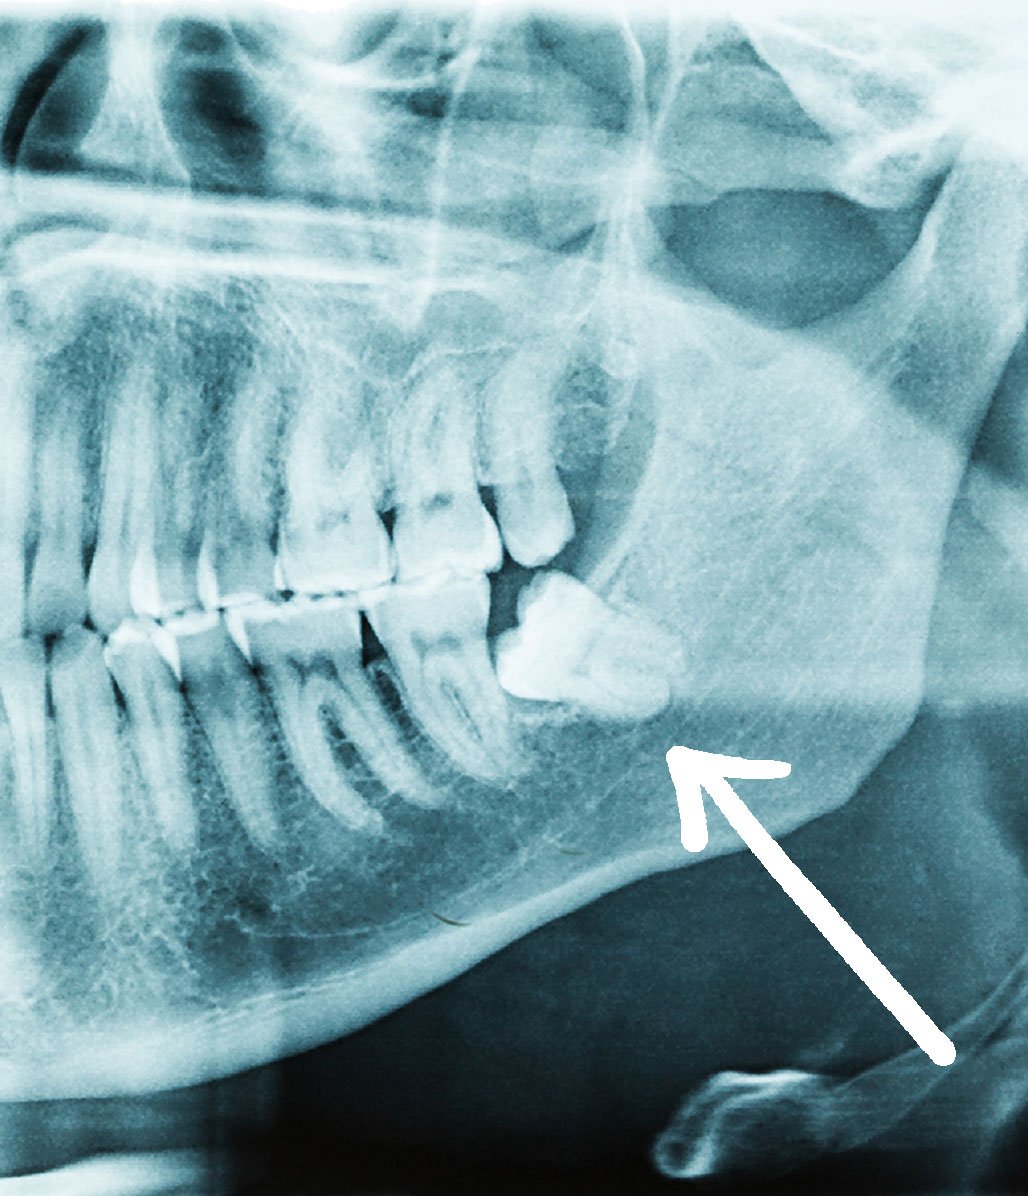

Sente desconforto ou dor no fundo da boca? Pode ser o siso pedindo atenção.

Ideal para casos de dor inflamação, dificuldade de higienização e falta de espaço.

Com foco em extrações de terceiros molares (sisos), Dr. Lucas também realiza procedimentos de frenectomia, gengivoplastia, remoção de cistos e tumores, além de próteses, clareamento, tratamento para bruxismo e restauração dental.